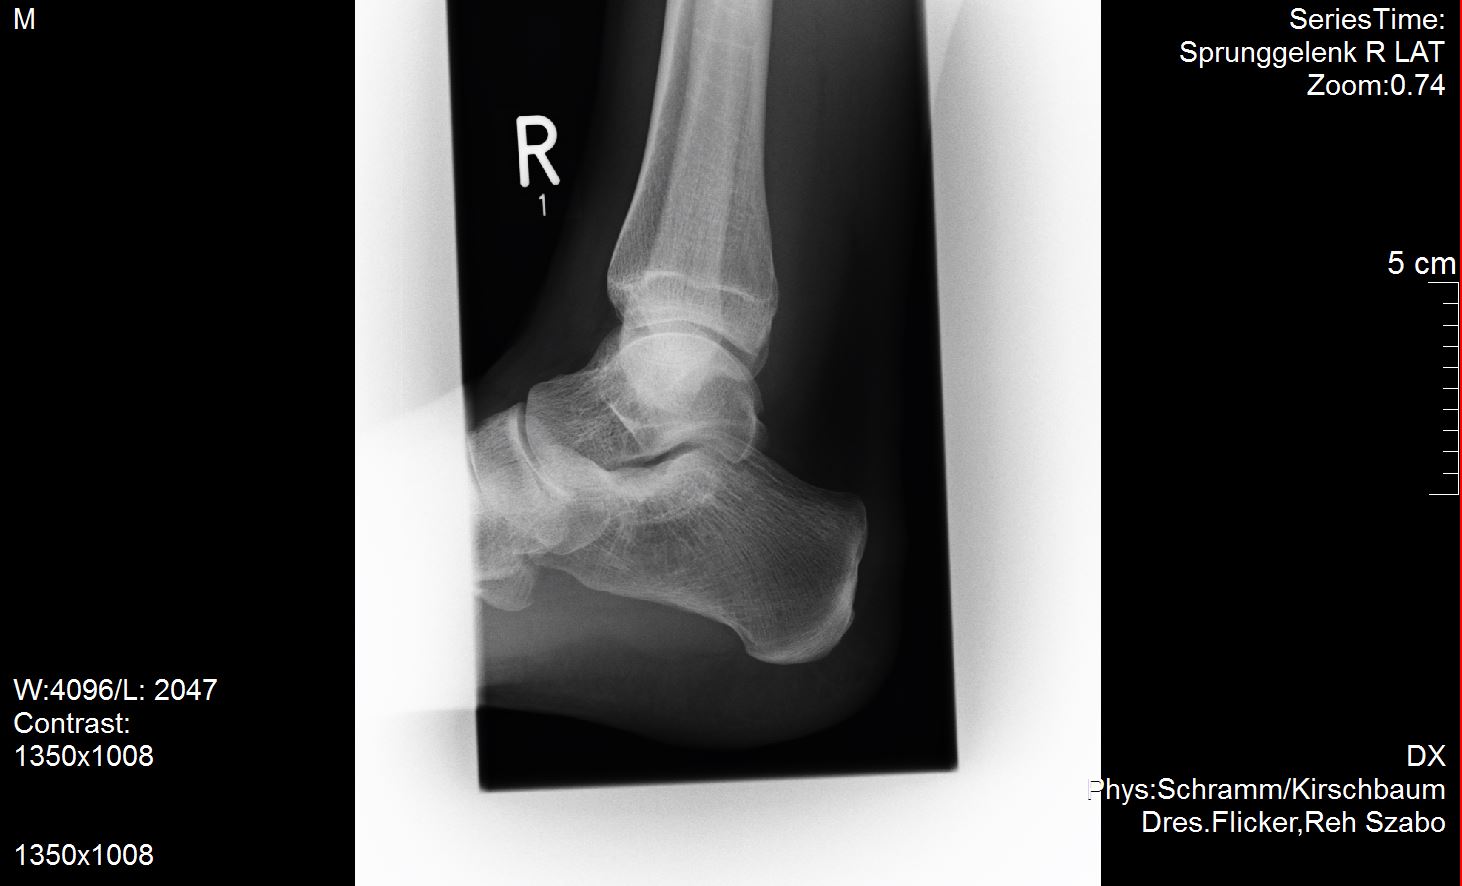

Ich versuche mal meine Röntgenbilder anzuhängen. Vielleicht ist ja ein Experte unter uns der dazu was sagen kann?

Ich habe außer dem mir diagnostizierten Spreizfuß nach oben stehende Zehen. Weiß nicht genau ob man dies Hammerzeh oder Krallenzeh nennt was ich habe aber es geht in die Richtung.